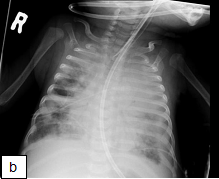

Figure 163a and b: (a) CXR taken pre-ART in a 4 month old child newly diagnosed with HIV infection. Xray shows: Multifocal airspace disease involving both upper lobes, right middle lobe, left lingular and left lower lobe. (b) CXR, 5 weeks post-ART initiation in the same child as above. He had been readmitted for worsening respiratory distress.

X-ray shows: Progressive air space disease with new more confluent left lower lobe, right lower lobe and right upper lobe consolidation plus a large pleural effusion with dense opacification of the left upper lobe as before.